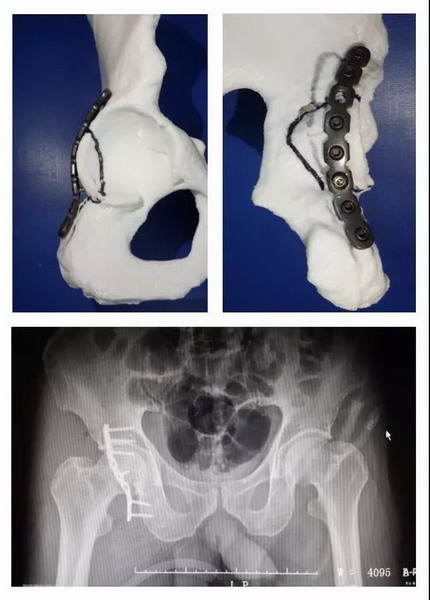

3D打印技术能让骨科手术实现“私人订制”

市民李先生因严重车祸导致全身多处受伤,其中髋臼(盆骨附近)骨折。常规手术需要选择医用钢板、螺钉等置入物,由于置入物是按一定规格批量生产,因此骨科医生只能依靠经验来选择最适合的,或现场进行塑型,调整成较为合适的尺寸。这样就使得手术时间长,复位固定过程难度很大。再加上髋臼周围的内外侧面有大量肌肉附着,并且有血管网形成,因此,手术难度系数较大。在江门市五邑中医院骨二科,医生借助3D打印技术,按照1:1的比例打印出完全相同的骨盆髋臼骨折模型,提前为患者选择适合的医用钢板、螺钉。术前进行模拟手术,提高手术效率,患者术后恢复良好。

区文欢主任说,借助3D打印技术,医生可以将患者CT扫描的数据,通过专用的软件分析,整合出患者关节组织全仿真信息,1:1打印出来,实现多维模拟,准确测量数据、设计手术方案。同时,利用计算机技术将骨折进行复位,然后再打印出一个复位好的1:1模型,在模型上进行内固定的预塑形,使内固定更贴合。这样可以节省时间、优化流程,使手术更精准,创伤也更小,减少手术感染几率。精准的钢板塑形还能使骨折端的复位不易丢失,特别在复杂的关节周围骨折、骨盆骨折、肩胛骨骨折等,应用3D打印技术有显著优势。

目前3D打印技术的辅助应用,主要是骨科中相对复杂、精细的手术,如骨盆骨折、髋臼骨折、上下肢复杂关节内骨折,以及复杂髋、膝关节翻修等。对外地患者的会诊,医院骨科也可以通过对方医院传来的患者影像数据,借3D打印机打印出仿真模型,以此为手术提供远程指导。“自2015年在我院应用以来,3D打印技术越来越成熟,在骨科领域的应用范围也越来越广泛,越来越多患者享受到这项技术带来的好处。”区文欢主任表示。